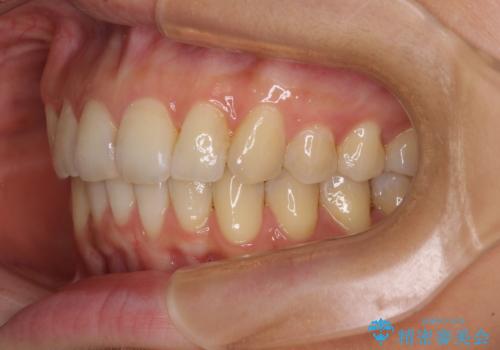

カリエールディスタライザーを併用したことで、確実かつ短期間で治療を終えることができました。